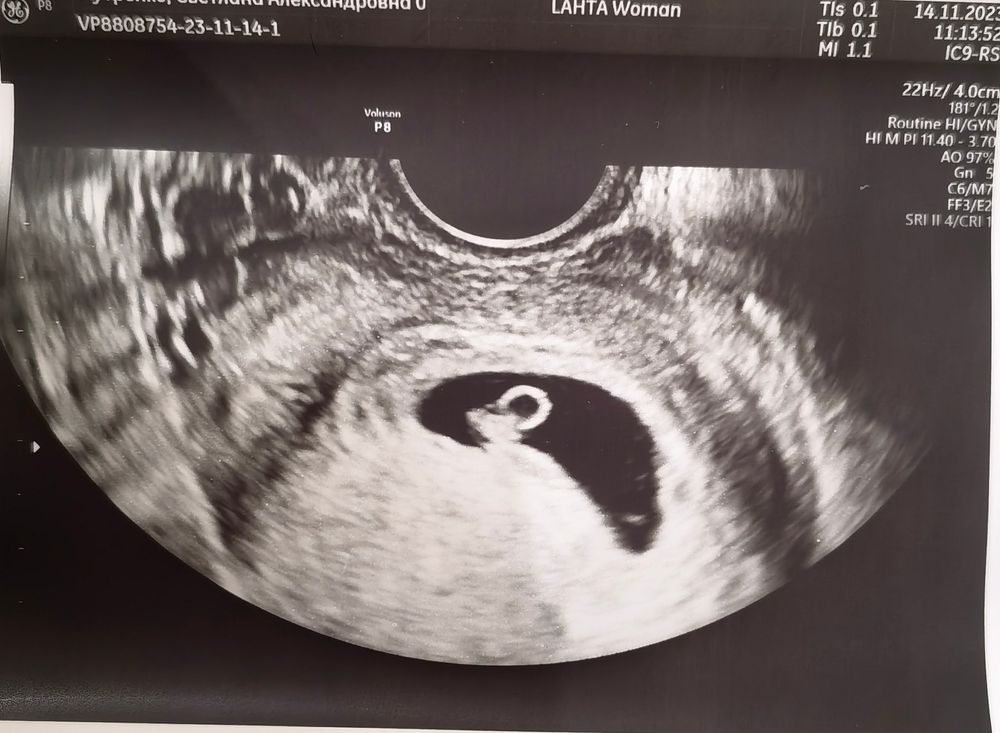

Второе УЗИ. Наверное, могу закрасить кружочек 💕

У вас с пгд эмбриончик? Поздравляю 🫶🏻 красивое «колечко» 💍

Екатерина, ДЯ+пгд, да. Все равно находила себе причины для тревог, даже из пальца высосанных, но тревог. Но я очень рада, что эти американские горки, вроде как, вышли на более ровную трассу. Надеюсь, нервняков такой амплитуда, как в первые недели, больше не будет 🥲